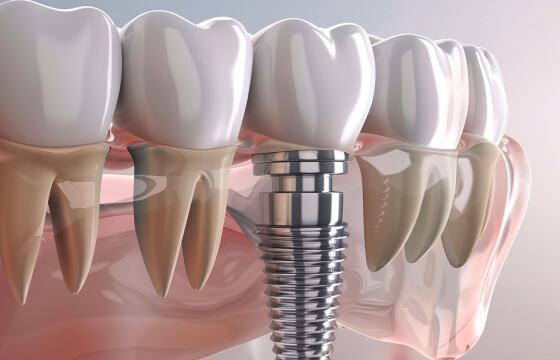

02デジタル技術の活用

CTやマイクロスコープなど、デジタル機器を駆使した精密な診査・診断を実施。感覚に頼らない、科学的根拠に基づいた治療で、健康な歯を最大限に残します。

03世界基準の当たり前の治療を

世界では当たり前になっている歯科治療は、まだまだ日本の当たり前の基準ではありません。年間を通して海外で学びを深めている理事長が自ら治療提供しています。

また、正確な診断と精密な治療を実現するために、歯科用CTやマイクロスコープなど、

世界基準の最新設備を完備しています。